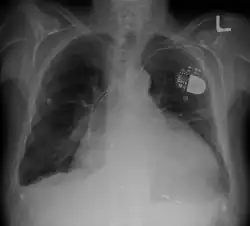

Chest radiography may reveal cardiomegaly, pneumonia, pleural effusion, and/or mediastinal widening.[4] Electrocardiogram (ECG) is a component of the diagnostic work-up which may suggest pericarditis as the underlying cause of symptoms. The ECG findings for purulent pericarditis are similar to those for other etiologies of pericarditis. ECG findings may include diffuse S-T segment elevation, diffuse T wave inversion, low QRS voltage, and/or electrical alternans.[4][6] Echocardiogram may be used to evaluate for fluid collection in the pericardial sac, and may be important in guiding therapy in patients with signs of cardiac compromise (i.e., cardiac tamponade).[3][7]

- Chest x-ray showing cardiomegaly, pulmonary infiltrates, pleural effusion(s), pericardial effusion, and/or mediastinal widening[4]

- Echocardiography (transthoracic or transesophageal) showing fluid accumulation in the pericardial sac surrounding the heart with possible evidence of cardiac tamponade